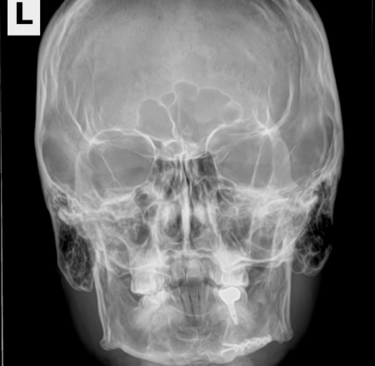

The story of how I got the x-ray or at least the whole scenario was kind of funny. I broke my pinky somehow at my friend's house in Oklahoma in the fall of 2023. When I went to the doctor they did an x-ray of my hand. I have a few metal parts in my head and then told them I got into a fight and thought I may have hurt some implants in my head. Not really but I just wanted these X-rays.